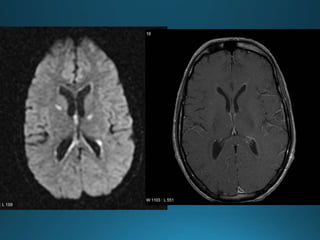

État criblé, also known as status cribrosum, is a term that describes the diffusely widened

perivascular spaces (Virchow-Robin spaces) in the basal ganglia, especially in the corpus

striatum. It is usually symmetrical, with the perivascular spaces showing CSF signal and

without diffusion restriction